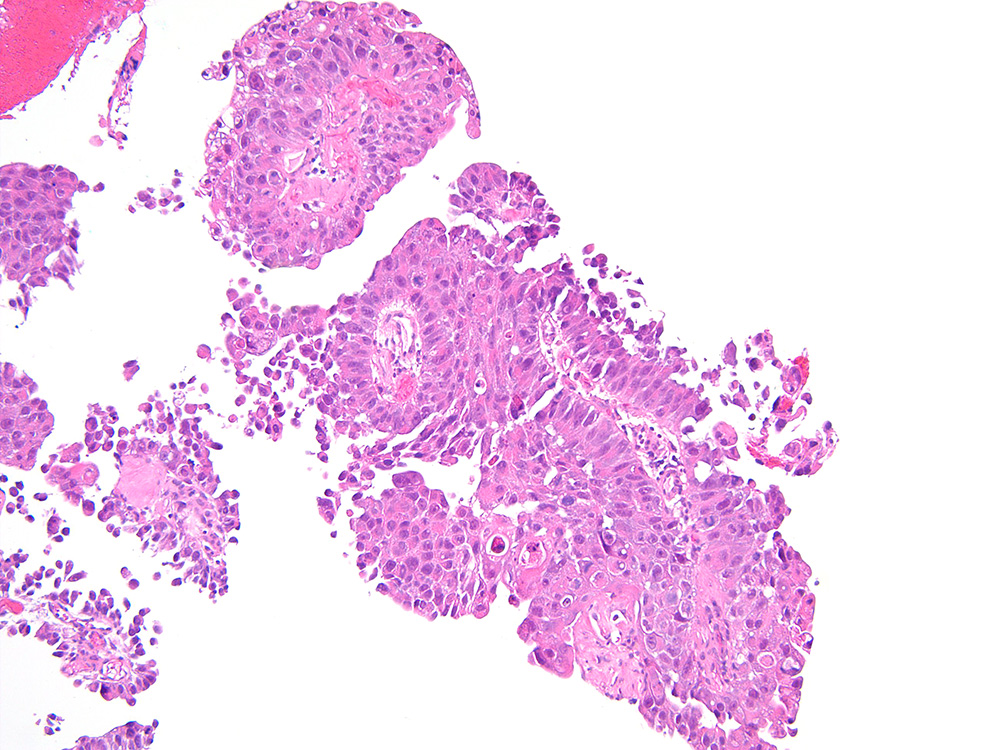

Bladder Papillary Lesions

Case ID: 273